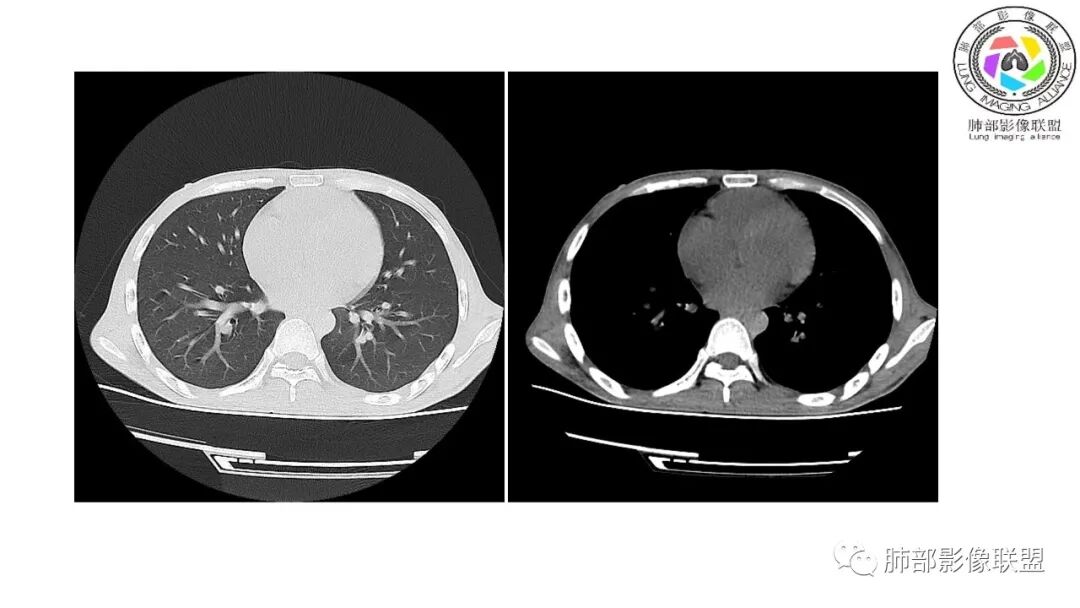

影像与临床:1.青年男性,HlV阳性,颜面部皮疹(未提供皮疹图像)、发热(高热),实验室CRP、PCT高,T-Spot阴性。2.右肺下叶空洞结节,壁厚不均,边界清楚,其内线状影,未见液平及钙化,未见卫星灶,纵隔淋巴结增大,双侧腋窝见增大淋巴结。心腔内低密度提示贫血可能。肝脾影增大,未见结节影及块影。腹膜后见多发增大淋巴结。

综合分析:本例肺部影像学改变并不具有特征性,空洞性病灶须与多种疾病鉴别,但年轻HIV阳性患者,高热,皮疹,肝脾增大,纵隔、腋窝、腹膜后见多发增大淋巴结等都强烈提示马尔尼菲篮状菌感染的可能性。